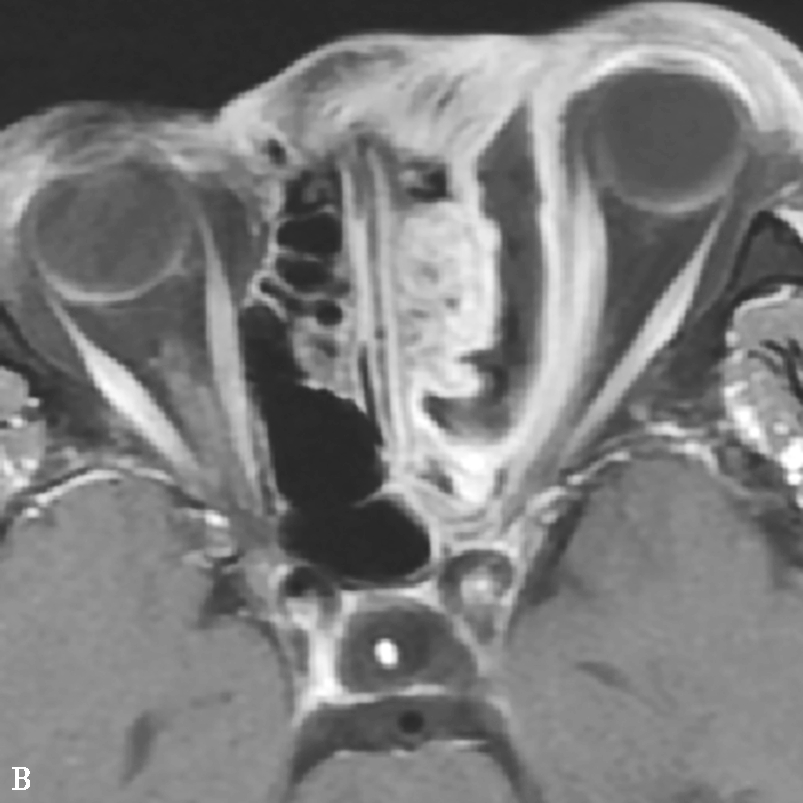

图1-3-23 急性侵袭性真菌性鼻窦炎

A、B.横断面、冠状面CT骨窗,示双侧蝶窦、后组筛窦软组织影,密度不均,窦壁骨质硬化伴局部骨质破坏,累及双侧圆孔、翼管;C~E.MRI横断面T 1 WI、T 2 WI、T 1 WI+FS+C,示双侧蝶窦、后组筛窦内混杂长T 1 、长T 2 信号,窦腔内见斑片状短T 1 、短T 2 信号影,增强扫描边缘强化,前颅底脑膜增厚强化

该病多发生于上颌窦和筛窦,其次为蝶窦,额窦罕见。早期表现为单侧鼻腔、鼻窦黏膜和软组织增厚,但无特异性,应密切结合临床考虑;Silverman等提出上颌窦周围脂肪间隙软组织浸润为该病较早的征象;典型表现为鼻窦内充以软组织影,窦壁及邻近颅面部骨质可出现广泛骨质破坏,但无窦腔变形,窦腔内一般无钙化;广泛侵犯眼眶、颞下窝、翼腭窝、硬腭、颅面部软组织等邻近结构,严重者可侵犯颅内,出现脑膜炎、脑炎、脑脓肿、脑梗死等(图1-3-23A、B)。

2.MRI表现

T 1 WI多为低或等信号,T 2 WI多为高信号,增强后有明显强化。MRI能更清楚显示眼眶、颅内、海绵窦等鼻外蔓延范围,为治疗方案选择提供依据,对术后随访也有很大帮助(图1-3-23C~E)。